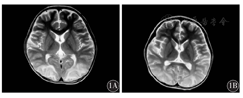

例1、例2及例3于HD-MTX化疗后24 h内均出现剧烈呕吐、腹痛,止吐、制酸处理不能缓解,例1出现肺水肿、肠麻痹、急性肾衰竭、严重口腔黏膜炎,查MTX血药浓度(44 h)高达36 μmol/L,血肌酐、尿素氮进行性升高;例2、例3出现抽搐,表现为神志丧失、双眼凝视上翻、四肢强直抽动,查MTX血药浓度均明显高于安全范围(用药24 h:例2为30.0 μmol/L,例3为136.5 μmol/L)。例4化疗期间MTX血药浓度处于安全范围,化疗后第7天出现剧烈呕吐、腹痛,继而出现血压升高、癫痫持续状态、严重低钠血症,颅脑磁共振成像(MRI)提示可逆性后部白质脑病综合征(RPLS)可能(图1A)。

1A:抽搐后第2天,双额顶叶皮层下白质,枕部深部白质,右侧脑室及小脑见多发异常信号影,未见明显强化,周围见片状水肿;1B:抽搐后2周,双顶枕叶侧脑室旁皮层下白质见对称性异常信号灶,T2呈高信号,T1呈低信号,较前范围明显缩小

转入重症监护室,例1、例2及例3进行高通量透析(HPD),大剂量CF解救,碱化、水化等治疗,例4予甲泼尼龙及美罗培南抗感染、呋塞米利尿等治疗,例2、例3予以镇静止惊、输血、集落刺激因子、抗感染等处理;例4进行控制血压、纠正电解质紊乱、抗癫痫等治疗,经以上处理后,例1、例2及例3血药浓度下降至安全范围,并发症治愈。例4抽搐停止,神志恢复,未遗留后遗症,复查颅脑MRI提示病灶吸收(图1B)。

RPLS是由多种原因引起的以神经系统受损为主要表现的综合征,神经影像学的典型表现为对称性的、大脑后部以白质为主的可逆性血管源性水肿[13]。抗肿瘤药物为诱发RPLS的常见原因,据统计,在RPLS的病因中细胞毒性药物占19%[14]。有研究表明,MTX的神经系统毒性反应与MTX的剂量及血药浓度并不相关,而可能与个体基因差异、药物相互作用及脑内维生素B12的低水平有关[15,16]。本组病例中,例4在HD-MTX化疗期间监测MTX血药浓度处于安全范围,在化疗后7 d出现神经系统损害,经头颅MRI诊断为RPLS,考虑可能与个体差异及其他化疗药物(化疗同时使用的长春新碱、培门冬酶、地塞米松等)的相互作用有关。